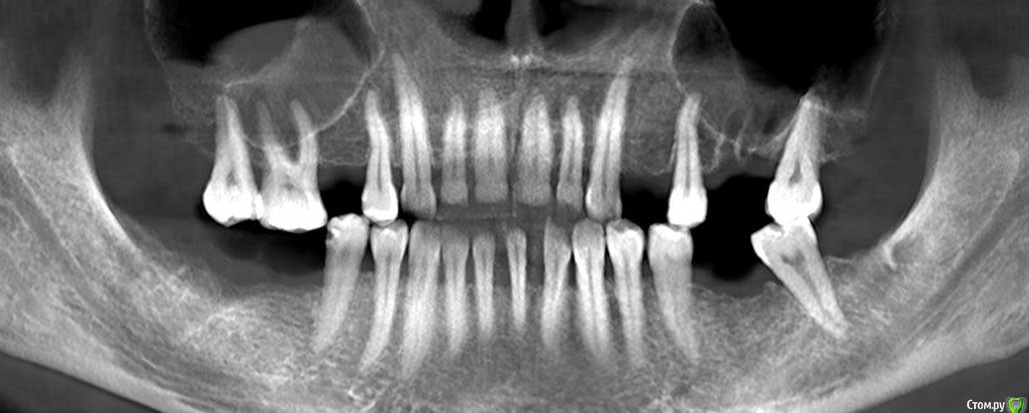

Irina_S Опубликовано 1 мая, 2017 Поделиться Опубликовано 1 мая, 2017 Уважаемые специалисты по жизненному циклу зубов и знатоки особенностей их поведения! Формулирую обращение именно так, потому что не знаю точно, какая именно стоматологическая специализация предполагает максимальную информированность по интересующему вопросу.Если ошиблась с выбором ветки форума, огромная просьба к модераторам перенести в нужное место! Моя история.В августе прошлого года был удалён нижний правый 7-й зуб. Была боль и опухание вокруг. Врач сказал, что ткани вокруг размягчены, оставлять нет смысла, будет плохо держаться. Зуб удалили, поставили дренаж. Десна затянулась за пару недель.В сентябре заболел верхний левый 6-й зуб. Была неудачная попытка лечения с диагнозом обострения периодонтита. При вскрытии каналов зуб был перфорирован и восстановлению по мнению всех врачей, у кого консультировалась, не подлежал. Удалили его в ноябре.Параллельно уже стала интересоваться имплантацией. Врач, удалявший зуб, сказал, что на это место раньше 4-х месяцев ставить ничего нельзя. Всё должно зарасти и уплотниться. Тем более, что десна там затягивалась гораздо хуже.В итоге из-за всех проводившихся манипуляций я с сентября почти всю пищу ем в измельчённом на блендере состоянии. Через блендер не проходят только те продукты, которые изначально не твёрдые и однородные. С левой стороны имеются соприкасающиеся 7-е зубы, но жевание ими больше дискомфортно, чем функционально. В остальных зубах, которые и до ухудшения жевательной способности не слишком сильно участвовали в пережёвывании, периодически появляются ощущения, которые сложно описать. Это не боль, а скорее больше похоже на что-то вроде онемения. Особенно чётко это ощущается по утрам после сна.Тем не менее, ситуация с моим питанием исключительно измельчённой едой, видимо, никаким образом не воспринимается серьёзно различными врачами, с которыми за это время общалась. Одни запросто предлагают перед имплантацией пройти курс ортодонтического лечения сроком не менее года. Другие говорят, что есть места, в которые нужно подсыпать костную ткань, и имплантацию там можно будет делать только через полгода, а это значит., что ещё плюс 3-4 месяца будет приживаться имплантат,, и только после этого появится хотя бы временная коронка.А ещё по мнению большинства ортопедов все коронки на имплантаты нужно ставить одновременно. То есть даже если где-то и можно установить имплантат раньше, то жевательная способность у восстанавливаемого зуба появится всё равно одновременно с остальными. В связи с этим у меня вопрос: как долго могут находиться зубы без жевательной нагрузки? Прикрепляю две панорамы из КТ с разницей в два месяца. Возможно, это поможет оценить какую-то динамику.Благодарю за терпение при прочтении и буду ещё больше благодарна за ответы! Ссылка на комментарий

колесников Опубликовано 1 мая, 2017 Поделиться Опубликовано 1 мая, 2017 Чем дольше будете ждать,тем меньше костной ткани будет в в областях предполагаемой имплантации,16,17 выдвинуться ещё больше,проблемы с внчс примут функциональные изменения. Необходимо имплантироваться как можно скорее ,если хотите несъёмные конструкции,либо съёмный протез на нч. Зубы 17,16 сильно выдвинулись,необходим очный осмотр. Самый сложный участок в плане имплантации ,область 26. Все решаемо. Ссылка на комментарий